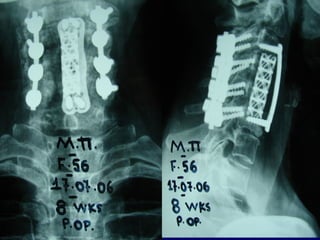

44thth

casecase

Diak. Nick.

M 61

possible origin

superficial skin infection at the elbow area

Symptoms

 High fever

 Back Pain

Laboratory

 E.S.R. 

 Leucocitosis 

 Neutro 

Posterior procedurePosterior procedure

Culture

Staph. aureous

Anterior procedureAnterior procedure

Follow upFollow up

Antibiotic treatment

Various schemes

 I.V. – Oral

for 6 months

Sufficient recovery